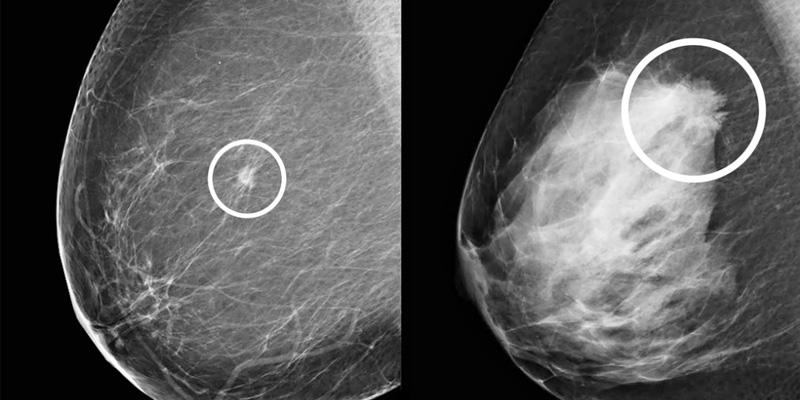

Mô vú dày đặc màu trắng trên phim chụp X-quang tuyến vú.

Làm giảm độ chính xác của chụp nhũ ảnh

Trong chụp X-quang tuyến vú, các mô tuyến và mô xơ – thành phần chính của mô vú dày đặc – thường hiển thị màu trắng. Điều đáng chú ý là các khối u hoặc tổn thương ung thư cũng có màu tương tự trên phim chụp. Sự “trùng màu” này khiến việc phát hiện bất thường trở nên khó khăn hơn, đặc biệt ở những người có mật độ mô cao.

Ngược lại, mô mỡ trong vú sẽ hiện lên màu tối hơn, tạo độ tương phản rõ rệt giúp bác sĩ dễ dàng nhận diện các khối u màu sáng. Vì vậy, phụ nữ có mô vú dày đặc thường cần kết hợp thêm các phương pháp chẩn đoán khác để tăng hiệu quả tầm soát.